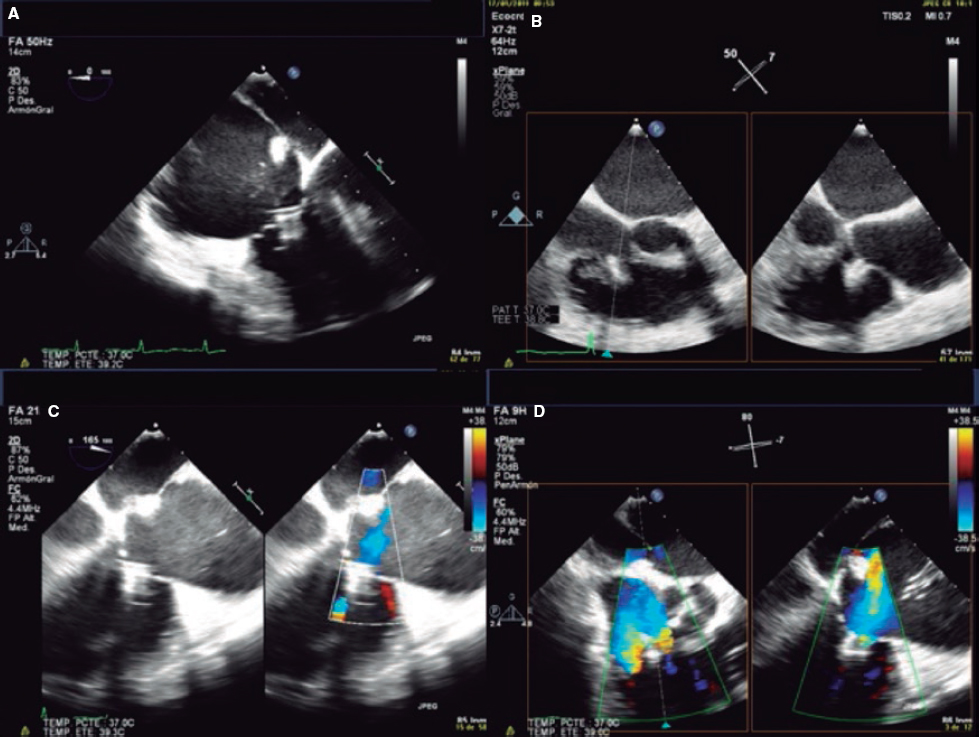

9. Once the leaflets have been captured, their insertion should be confirmed through multiple 2D TEE views. Also, the presence of tissue bridges should be verified (though 3D TEE views). Multiplane is very useful for assessment purposes. A TTE or an intracardiac echocardiography should be used in cases of uncertain leaflet insertion. The TV mean gradient should be measured to discard stenosis; in general, mean gradients > 3 mmHg are not recommended (figure 8).

Figure 8. A-D: grasping assessment in multiple views for leaflet insertion assessment and reduction of tricuspid regurgitation.

10. Standard release of the clip. Once it has been completely released, the degree and location of residual TR and need for new clip implantation should be assessed. The position of the new clips will depend on the location and amount of residual TR jets.